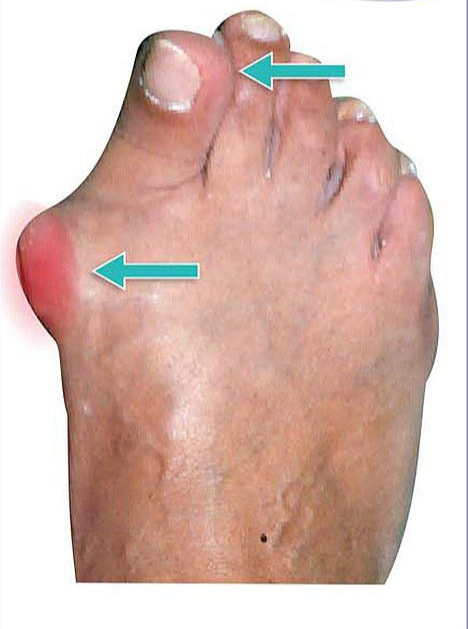

이러한 변형 자체는 크게 문제가 없으나, 변형으로 인해 계속되는 중족골 원위부 내측의 마찰로 인하여 굳은살이 생기고

심한경우 엄지발가락이 두번째 발가락을 침범하게 됩니다.